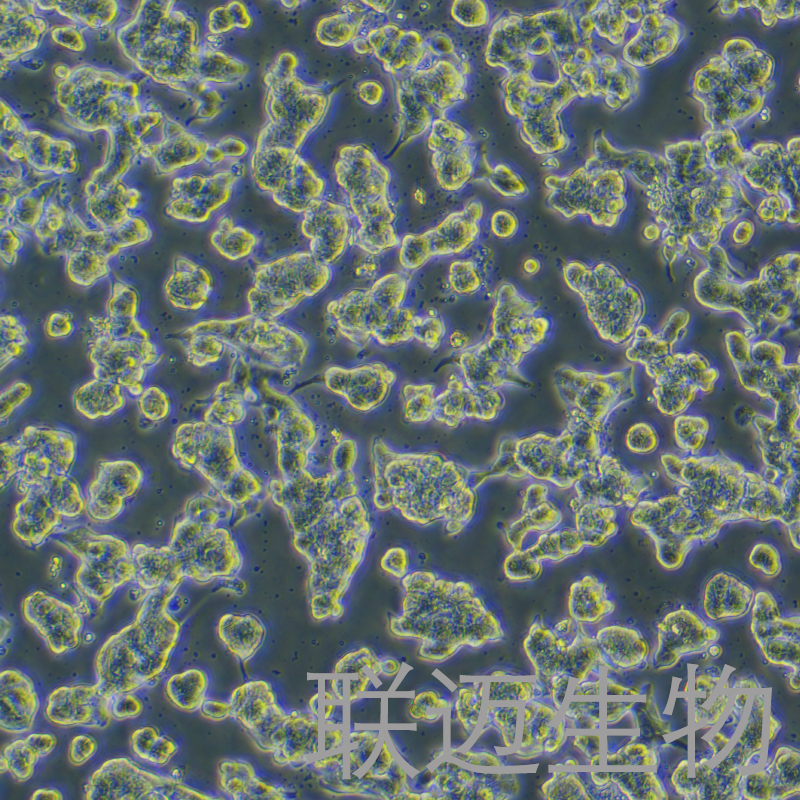

细胞系: 肿瘤细胞细胞形态: 上皮细胞样

上皮细胞样

SNU-719细胞来自韩国53岁男性原发性腺癌患者的胃组织。使用光学和电子显微镜进行形态学研究,通过放射免疫测定法测定上清液和细胞裂解物中的CEA,α FP和CA 19-9和TPA。筛选p53和c-Ki-ras基因突变并通过测序确认。来源于中等分化的肿瘤的细胞系以弥漫性单层形式生长,而来自分化差和最小纤维增生的肿瘤的细胞系仅作为非贴壁生长。SNU-719细胞系在细胞裂解物和上清液中均具有高浓度的TPA,p6突变(75%)。使用限制性核酸内切酶HinfI和多态性DNA探针ChdTC-15和ChdTC-114的DNA图谱显示出不同的独特模式;这表明这些细胞系是独特的,没有交叉污染。我们相信新表征的胃癌细胞系将为人类胃癌相关研究提供有用的体外模型。